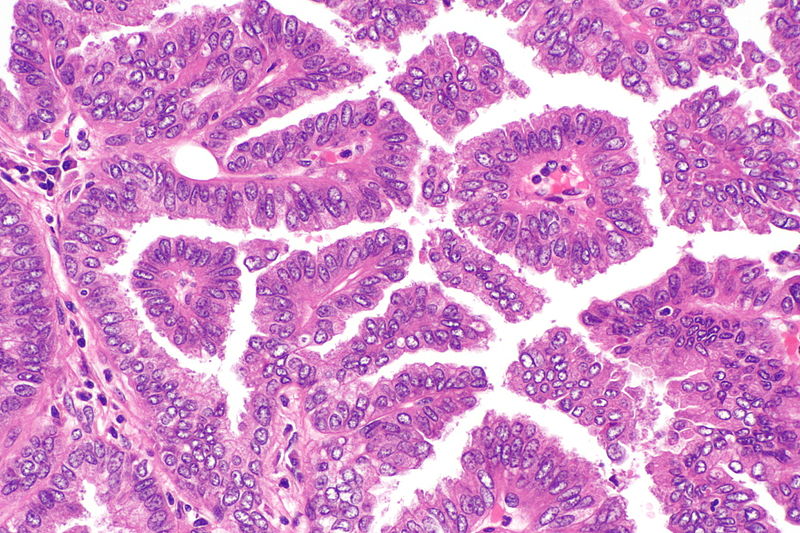

ΠΠ°ΡΡΠΈΠ½ΠΎΠΌΡ Π½Π°Π·ΡΠ²Π°ΡΡΡΡ Π² Π·Π°Π²ΠΈΡΠΈΠΌΠΎΡΡΠΈ ΠΎΡ ΡΠΎΠ³ΠΎ, ΠΊΠ°ΠΊ ΠΊΠ»Π΅ΡΠΊΠΈ Π²ΡΠ³Π»ΡΠ΄ΡΡ ΠΏΠΎΠ΄ ΠΌΠΈΠΊΡΠΎΡΠΊΠΎΠΏΠΎΠΌ. ΠΠ»ΠΎΡΠΊΠΎΠΊΠ»Π΅ΡΠΎΡΠ½Π°Ρ ΠΊΠ°ΡΡΠΈΠ½ΠΎΠΌΠ° ΠΈΠ»ΠΈ ΠΏΠ»ΠΎΡΠΊΠΎΠΊΠ»Π΅ΡΠΎΡΠ½Π°Ρ ΠΊΠ°ΡΡΠΈΠ½ΠΎΠΌΠ° β ΡΡΠΎ Π½Π°Π·Π²Π°Π½ΠΈΠ΅ ΡΠΈΠΏΠ° Π½Π΅ΠΌΠ΅Π»ΠΊΠΎΠΊΠ»Π΅ΡΠΎΡΠ½ΠΎΠ³ΠΎ ΡΠ°ΠΊΠ° Π»Π΅Π³ΠΊΠΎΠ³ΠΎ, ΠΏΡΠΈ ΠΊΠΎΡΠΎΡΠΎΠΌ ΠΊΠ»Π΅ΡΠΊΠΈ Π½Π°ΠΏΠΎΠΌΠΈΠ½Π°ΡΡ ΠΏΠ»ΠΎΡΠΊΠΈΠ΅ ΠΊΠ»Π΅ΡΠΊΠΈ (Π½Π°Π·ΡΠ²Π°Π΅ΠΌΡΠ΅ ΠΏΠ»ΠΎΡΠΊΠΎΠΊΠ»Π΅ΡΠΎΡΠ½ΡΠΌΠΈ ΠΊΠ»Π΅ΡΠΊΠ°ΠΌΠΈ ), ΠΊΠΎΡΠΎΡΡΠ΅ Π²ΡΡΡΠΈΠ»Π°ΡΡ Π΄ΡΡ Π°ΡΠ΅Π»ΡΠ½ΡΠ΅ ΠΏΡΡΠΈ. ΠΡΠΎ ΡΠ°ΡΠΏΡΠΎΡΡΡΠ°Π½Π΅Π½Π½ΡΠΉ ΡΠΈΠΏ ΡΠ°ΠΊΠ° Π»Π΅Π³ΠΊΠΈΡ Π² Π‘ΠΎΠ΅Π΄ΠΈΠ½Π΅Π½Π½ΡΡ Π¨ΡΠ°ΡΠ°Ρ .

Ρ63, Ρ40, ΡΠΈΡΠΎΠΊΠ΅ΡΠ°ΡΠΈΠ½ 5/6, TTF-1 ΠΈ Π½Π°ΠΏΡΠΈΠ½ Π β ΡΡΠΎ ΡΠΏΠ΅ΡΠΈΠ°Π»ΡΠ½ΡΠ΅ ΡΠ΅ΡΡΡ, ΠΊΠΎΡΠΎΡΡΠ΅ ΠΈΠ½ΠΎΠ³Π΄Π° ΠΈΡΠΏΠΎΠ»ΡΠ·ΡΡΡ ΠΏΠ°ΡΠΎΠ»ΠΎΠ³ΠΎΠ°Π½Π°ΡΠΎΠΌΡ, ΡΡΠΎΠ±Ρ ΠΎΡΠ»ΠΈΡΠΈΡΡ Π°Π΄Π΅Π½ΠΎΠΊΠ°ΡΡΠΈΠ½ΠΎΠΌΡ ΠΎΡ ΠΏΠ»ΠΎΡΠΊΠΎΠΊΠ»Π΅ΡΠΎΡΠ½ΠΎΠ³ΠΎ ΡΠ°ΠΊΠ°.